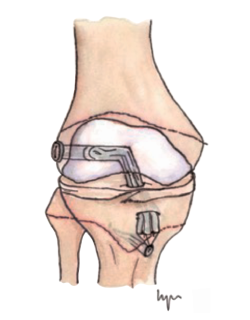

Otra de las técnicas de ahorro fisario es la llamada all epiphyseal. La primera de estas técnicas fue descrita por Anderson(13)(Figura 4) y está indicada en pacientes en estadio de Tanner I, II o III. Se realiza evitando la invasión de la fisis por parte de los túneles, utilizando injerto cuadrifascicular de isquiotibiales, que son estabilizados en el fémur mediante un sistema de tenosuspensión cortical y en la tibia con un tornillo interferencial distal a la fisis (Figura 5). Los resultados en un grupo de 12 pacientes fueron buenos, pero refieren que la técnica es compleja y demandante para un cirujano no experto en rodilla. Esta técnica minimiza el daño fisario, es anatómica y reproduce la isométrica(71). Se ha descrito la aparición de una deformidad angular relacionada con una epifisiodesis secundaria por sobretensionado de la plastia. En la actualidad, se han descrito multitud de modificaciones de esta técnica(15,72,73,74)(Figura 6).

Figura 6. Esquema de las modificaciones técnicas de la técnica todo epifisaria. A: técnica All-inside de Arthrex®; B: OrthoPediatrics®.

Lawrence et al.(72) realizan un túnel femoral paralelo a la fisis y otro túnel tibial central, ambos asistidos por tomografía computerizada intraoperatoria y reconstrucción 3D para comprobar que no se invaden las fisis. La fijación del autoinjerto de 4 fascículos se realiza con tornillos interferenciales.

McCarthy et al.(15) modificaron la técnica anterior utilizando los mismos principios. Sin embargo, el autoinjerto se fija con un sistema de suspensión cortical en ambos lados, femoral y tibial. De esta forma, evitan la colocación de un tornillo interferencial en hueso esponjoso epifisario y facilitan la reproducción anatómica de la huella del LCA nativa.

González et al.(74) realizaron un estudio multicéntrico, recogiendo 18 casos con buenos resultados funcionales y artrométricos.

Placella(75) presentó un estudio en 24 pacientes confirmando los buenos resultados y la satisfacción de los pacientes con la técnica all-inside, con un retorno precoz a la práctica deportiva.